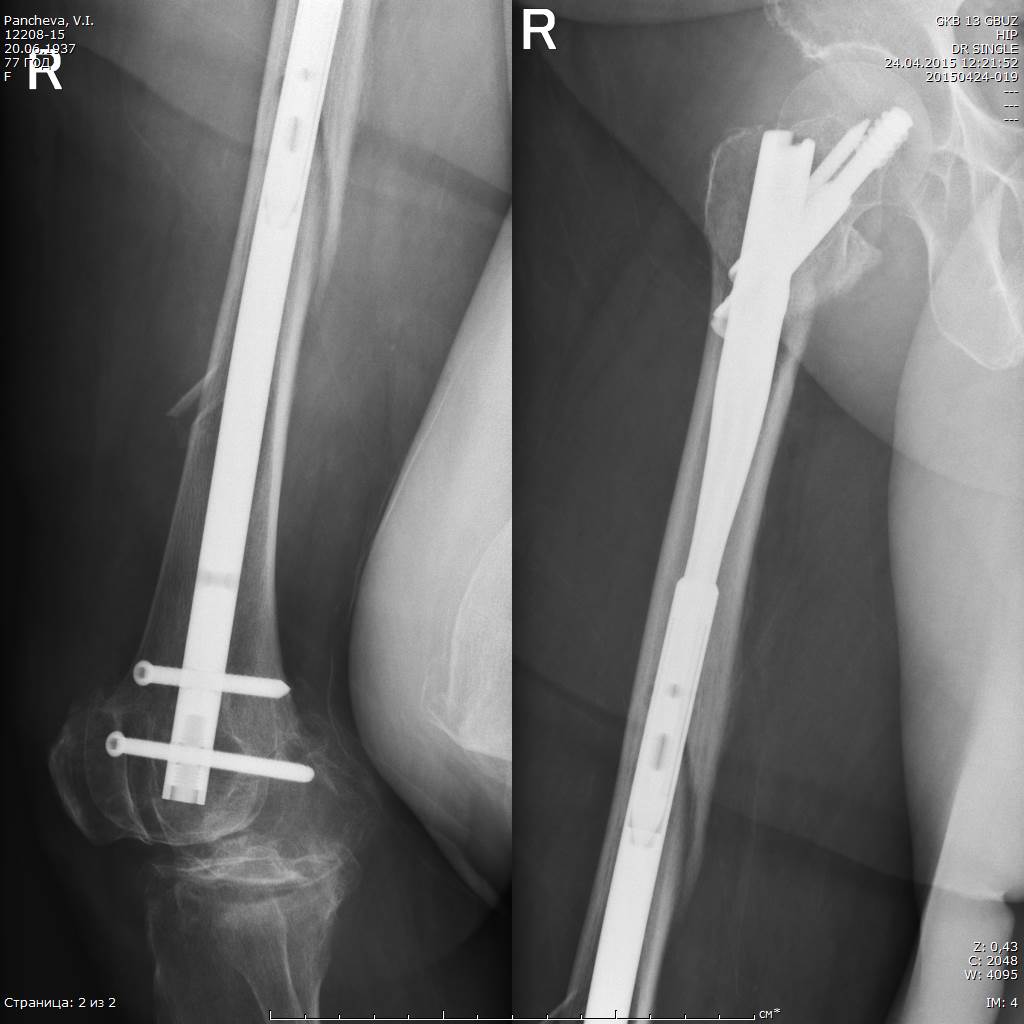

При планировании операции мы с коллегами исходили из следующих посылов:

1. Операция, по возможности, должна быть минимально травматичной и занять наименьшее количество операционного времени. Кровопотеря крайне нежелательна, даже небольшая

2. Операция, по возможности, должна дать пациентке шанс ходить с минимальным использованием дополнительной опоры. Костыли по её кондициям невозможны.

Именно исходя из пункта два был выбран вариант интрамедуллярного ревизионного остеосинтеза.

Вопросы вызывала только необходимость удаления аугментированного клинка, так как такого опыта у нас (в стране?) пока ещё не было. Конечно, в зарубежных статьях я видел, что это возможно, но тем не менее...

А тем не менее клинок, очевидно, благодаря режущим кромкам каждого из отверстий, через которые цемент и попадает в головку и шейку бедра, удалился безо всякого напряжения.

Цемент реально был "срезан" и остался в головке/шейке.

Ну, а установить новый длинный гвоздь такого же диаметра - не проблема, естественно

Новый клинок так же пришлось аугментировать 3 мл специального цемента.

На момент - пациентка достаточно активна, сидит в кровати подолгу, ходит по палате с методистом.